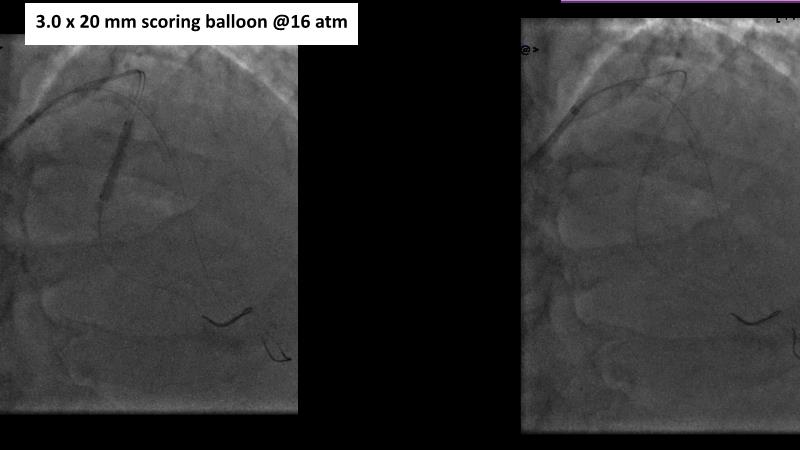

Sirolimus-coated balloon: expanding the scope of indications for complex coronary artery disease treatment

Watch this session to gain case-based insights on using DCBs in complex settings. Learn valuable tips and tricks for optimal DCB application, including the best timing and situations for their use. Discover how to effectively implement a hybrid strategy that combines DES and DCB when needed.

- To get a case based experience on how to use a DCB in complex settings